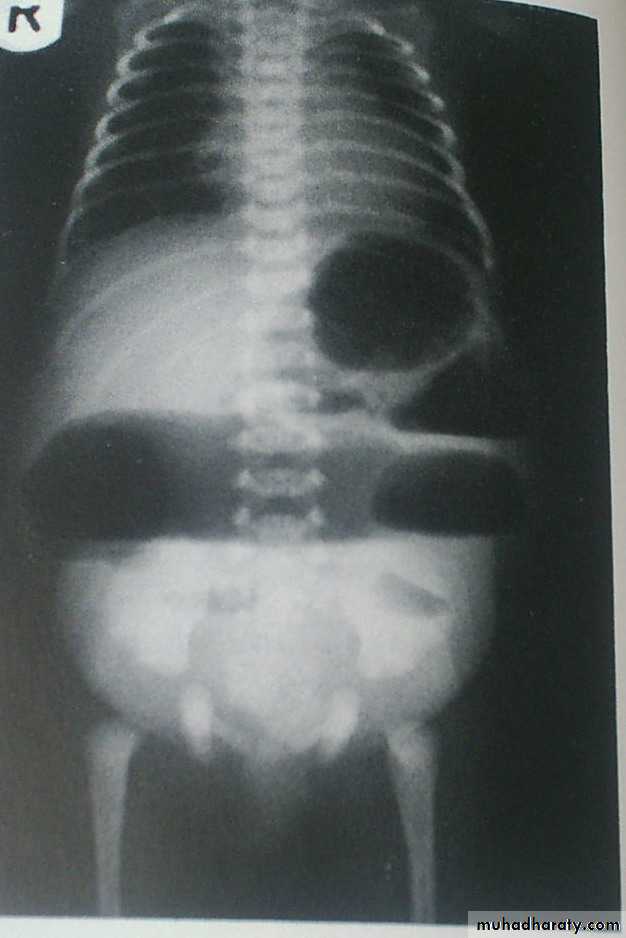

Pathology: dilated segment of ileum containing impacted black-green meconium .Proximal to this segment there are several loops of hypertrophied bowel distended with fluid .Distal to the obstruction there is a few separated gray white globular pellets in the distal ileum .

Clinically: abdominal distension ,vomiting , & failure of passing meconium .

• Investigation:

• 1.Plain X-ray :

• multiple air fluid level .

• soap bubble appearance

• speckled peritoneal calcification